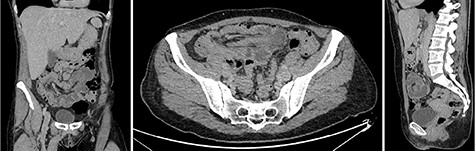

A 51-year-old female patient presented to the emergency department with abdominal pain that started and increased significantly within 1 day. The abdominal pain was described as crampy, appearing first in the periumbilical region with migration to the right lower quadrant. In addition, the patient experienced nausea, but no vomiting and had diarrhea twice that day without blood admixture. The patient’s past medical and family history were unremarkable. In physical examination, the abdomen was non-distended and soft but with rebound tenderness, especially in the right lower and middle quadrant. The rectum was empty and there was no indicator of intestinal hemorrhage. Laboratory tests showed a white blood cell count of 14.5 × 109/L and a C-reactive protein level of 7.0 mg/L. All other studies were within normal limits. An abdominal ultrasound showed a ‘pseudokidney’ sign in the lower abdomen (Fig. 1). Additionally, a computerized tomography (CT) scan of the abdomen and pelvis was performed and revealed an intussusception involving ~20 cm of the ascending and transverse colon (Fig. 2).

Abdominal ultrasound showed a ‘pseudokidney’ sign on the longitudinal view of the lower abdomen.

Intravenous contrast-enhanced abdominal and pelvic CT scan showed the full extent of the colocolic intussusception. No lead point was evident. (Left) Coronar view with ‘sausage’-shaped lesion. (Middle) Axial view with ‘sausage’-shaped lesion. (Right) Sagittal view with ‘targed’-shaped lesion.